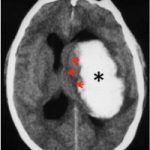

Existen dos tipos de ACV: el isquémico, que representa el 80% de los casos y sucede cuando hay una obstrucción en un vaso sanguíneo cerebral. El otro tipo es el hemorrágico, que representa el 20%, y es ocasionado por la ruptura de un vaso sanguíneo.

Isquémico

Hemorrágico